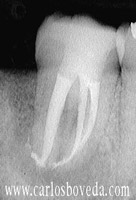

Video de un Retratamiento de Conductos en Una Sesión - (formato Quicktime)